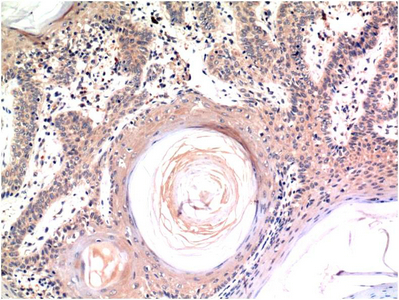

Caspase-3 mouse Monoclonal Antibody(4B8)

Application

| IHC-P |

| Dilution | IHC-P~~IHC 1:100-200 |

| Reactivity | Human, Rat, Mouse |